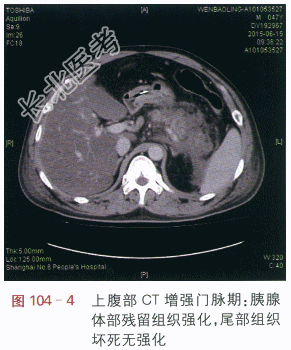

读片分析:CT平扫:胰腺体尾部肿胀,密度减低,边缘模糊,周边见流出影,左肾前筋膜肥厚(见图104-1)。附见:肝脏密度减低。CT增强扫描:胰腺体尾部呈低密度,边缘模糊,胰腺体部残留组织强化,尾部组织坏死无强化(见图104-2~图104-4)。